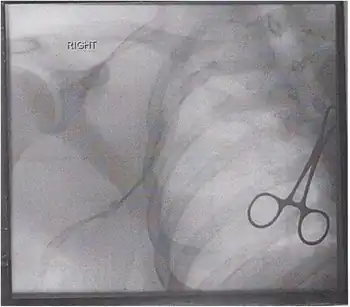

Paget-Schroetter syndrome -Prethrombolysis venogram